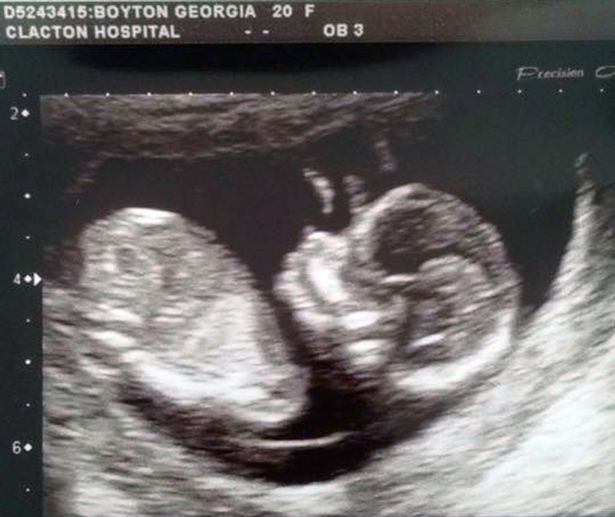

Georgia azt állítja, James szerette volna a helyi kórházba vinni a nőt, de elutasították, mivel a One to One Midwives nevű szülésznői szervezet gondozásában állt. – Úton az ultrahangra pánikba estem, és hamarosan megkaptuk az eredményt, miszerint Dollie Raie-nek nem ver a szíve. A következő néhány óra elhomályosul. Elviselhetetlen volt a gondolat, hogy a lányom halott bennem. A kislány Március 6-án, a korai órákban született meg, 2900 grammal.